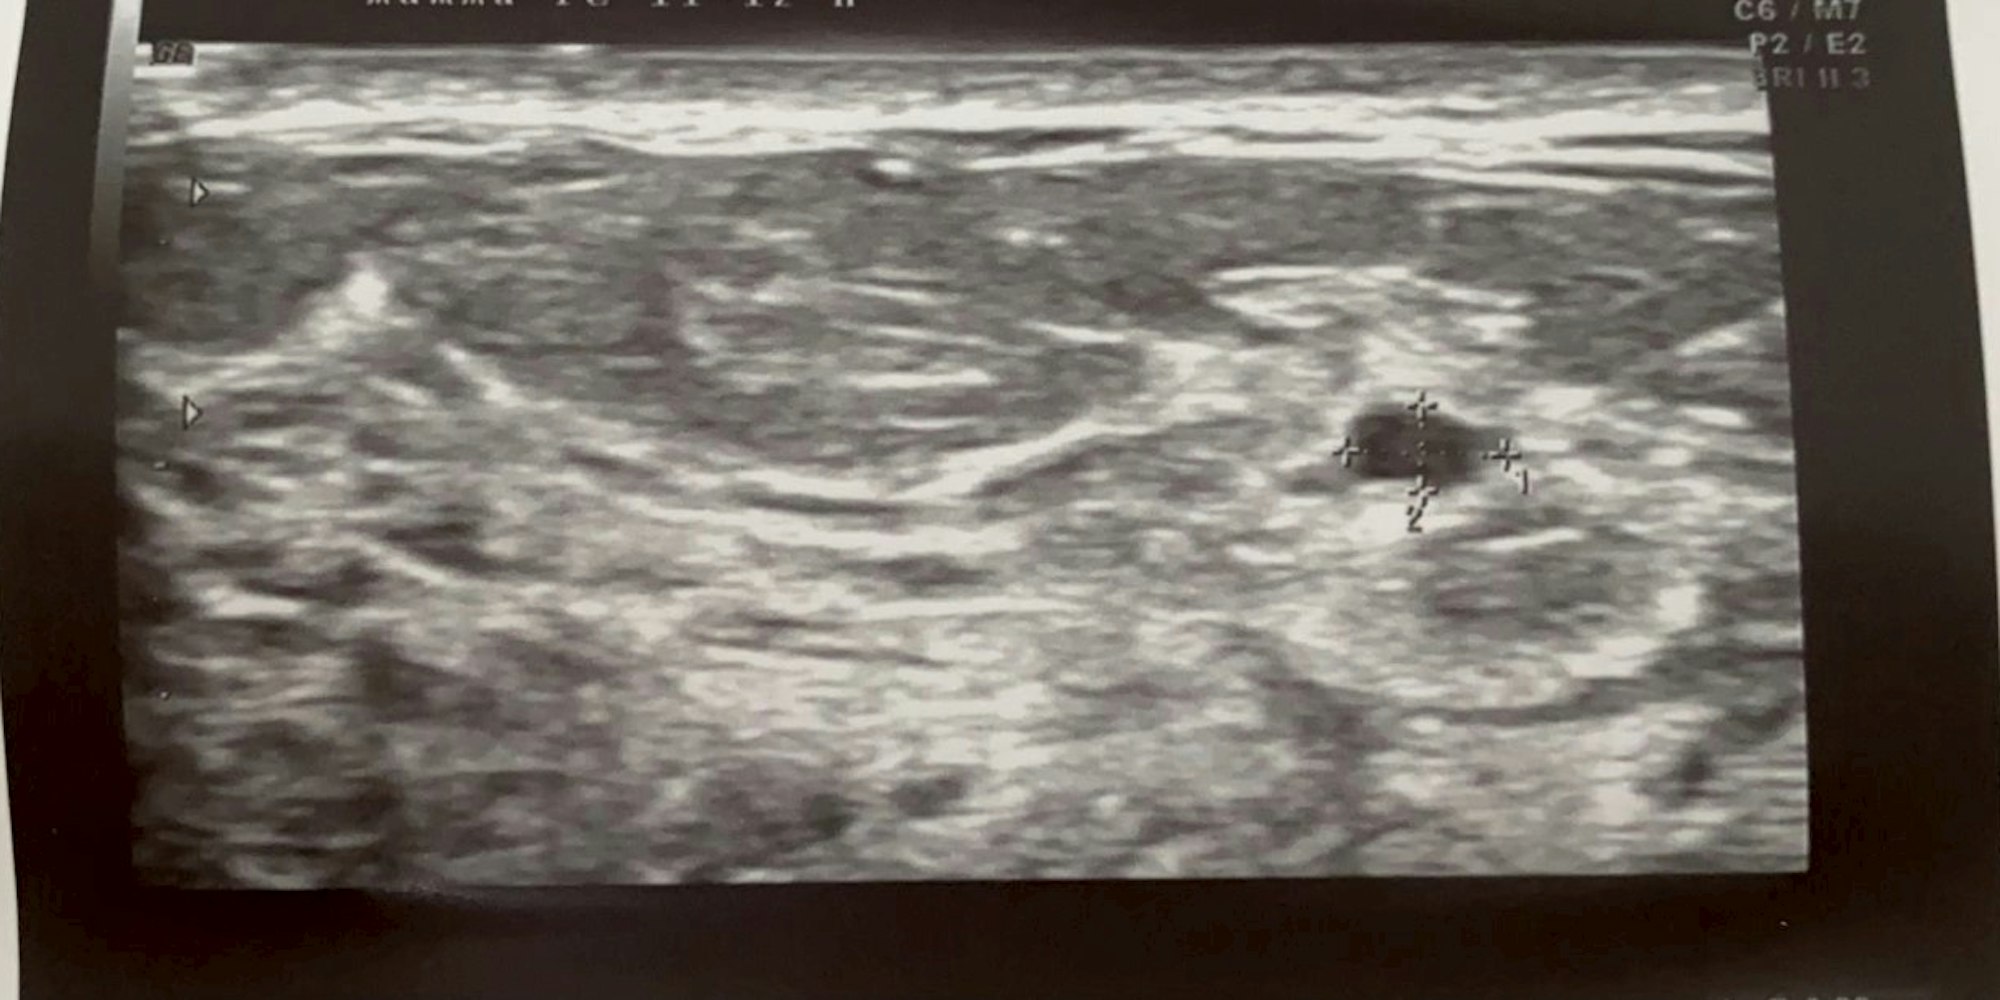

Das Ultraschall-Bild mit der verdächtigen Zyste.

Köln 50667: Ultraschall-Bild schockiert Soapstar Carolina Noeding

Carolina erleichtert: „Ich kann wieder durchatmen. Es wurde nur eine Zyste gefunden. Die weiteren drei haben sich mit Blick auf die tiefere Schicht aufgelöst. Da mein Brustgewebe so dicht ist, bietet das Ultraschall-Bild leider Raum für Interpretationen. Aber es haben jetzt sechs Fach-Augen draufgeschaut. Und die Ärzte sagen, ich solle mich beruhigen und erst in einem halben Jahr wiederkommen.“